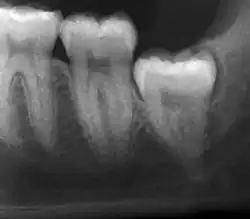

If the tooth cannot be assessed with clinical exam alone, the diagnosis is made using either a panoramic radiograph or cone-beam CT. Where unerupted wisdom teeth still have eruption potential several predictors are used to determine the chance of the teeth becoming impacted. The ratio of space between the tooth crown length and the amount of space available, the angle of the teeth compared to the other teeth are the two most commonly used predictors, with the space ratio being the most accurate. Despite the capacity for movement into early adulthood, the likelihood that the tooth will become impacted can be predicted when the ratio of space available to the length of the crown of the tooth is under 1.[5]: 141